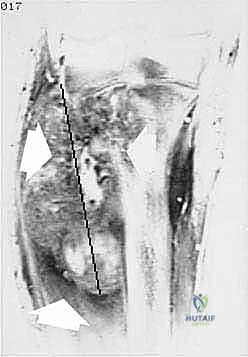

- التصوير بالرنين المغناطيسي (MRI): هو المعيار الذهبي لتقييم أورام العظام والأنسجة الرخوة. يوضح للدكتور هطيف الامتداد الدقيق للورم داخل نخاع العظم ومدى غزو العضلات والأوعية الدموية المجاورة.

- الخزعة (Biopsy): الخطوة الأهم لتأكيد التشخيص. يقوم الدكتور هطيف بإجراء خزعة بالإبرة الأساسية (Core Needle Biopsy) بدقة متناهية، مع مراعاة أن يكون مسار إبرة الخزعة ضمن المنطقة التي سيتم استئصالها لاحقاً أثناء البتر، لمنع انتشار الخلايا السرطانية.